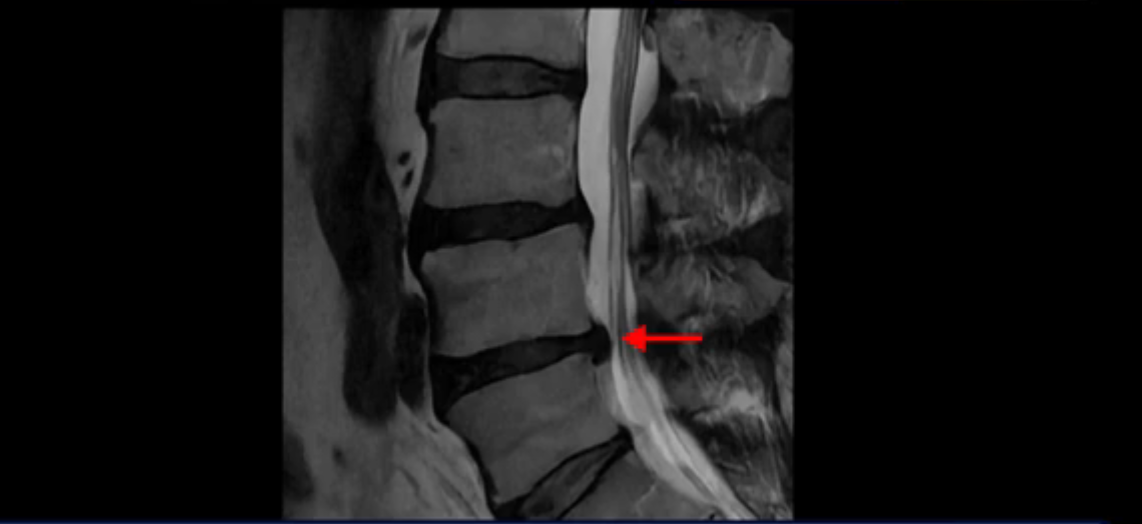

이분 MRI를 잠깐 보실까요? 보시면 두 마디가 특히 안 좋은데 3번 4번 디스크가 터져서 흘러 내려 있습니다.

그런데 이분은 4번 5번에도 디스크 파열이 있습니다.

가운데로 심하게 밀려 나와 있는데요.

또 4번 5번에는 협착으로 척추관이 많이 좁아져 있습니다.

또 왼쪽 신경 가지들이 빠져 나가는 신경구멍들이 여러 마디가 좁아져 있습니다.

이런 이유들 때문에 왼쪽 엉덩이부터 종아리, 발가락까지 저리고 아픈 겁니다. 그래서 서둘러 병원에 가셨는데요. 그래서 서둘러 병원에 가셨는데요. 여러분이 꼭 아셔야 할 게 이렇게 다리가 심하게 저리고 아프면 X-ray만 찍을 게 아니고 MRI를 찍어 보시는 게 맞습니다. X-ray로는 디스크가 터졌는지 신경구멍이 좁아진 협착이 있는지를 정확히 할 수가 없습니다. 그래서 이분은 당장 아픈데 해결이 안 되니까 제주도에서 유명하다는 한의원으로 갔습니다.